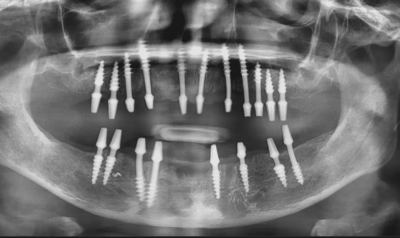

3. The phase of recovery

The jawbone will develop and fuse with the surface of the dental implant throughout this procedure. This procedure is also known as osseointegration because it provides a strong foundation for the new artificial tooth, just like roots provide for natural teeth. This procedure typically takes 3 to 6 months, depending on bone health and shape. When patients have adequate bone structure, the entire treatment can be finished in one day. The second operation can then be scheduled, but only after the implants have merged with the bone. Your dentists will do an x-ray to determine whether the implant is suitable for the second procedure.

Dental implants have emerged as the most promising option for replacing lost teeth. If most or all of your teeth are missing, treatments such as all-on-four and all-on-six can help you acquire complete mouth dental implants with 4 or 6 titanium posts on your jaw bone.